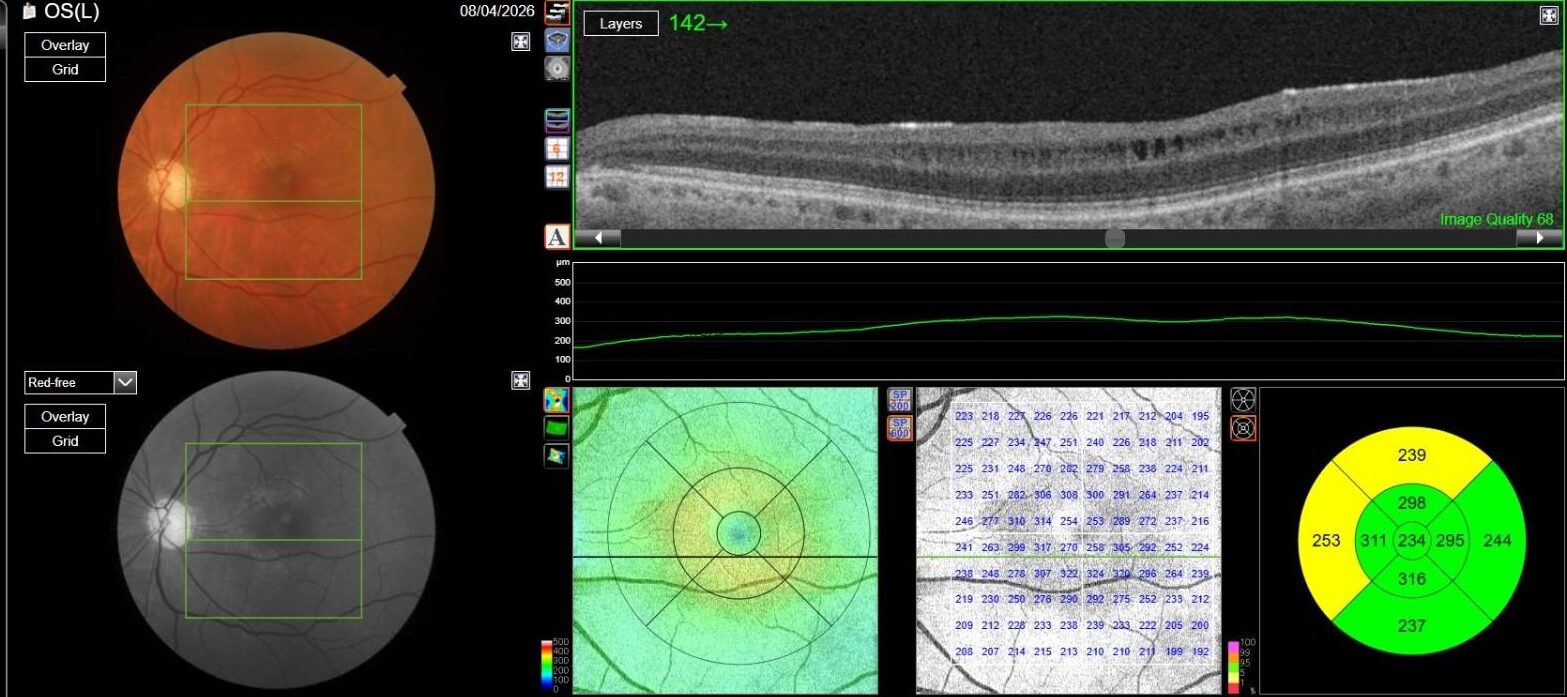

OCT in OD was normal, while in OS it showed multiple, well-defined small hyporeflective cystic spaces localized to the inner retinal layer (INL) in the perifoveal area, alongside with extreme thinning of the retinal nerve fiber layer (RNFL), whose profile and reflectivity were barely noticeable.

Optic Disc OCT with RNFL thickness quantification was performed as well; while in OD it revealed a minimal RNFL defect, in OS it showed extensive and severe RNFL thinning in all sectors, which was also confirmed on GCL+/GCL++ analysis by means of a 3D macula scan.

OCT-A was also performed in OS and, as expected, turned out to be negative. This also allowed an OCT en-face acquisition and subsequent segmentation at INL, which clearly showed the perifoveal distribution pattern of the INL cystic spaces previously found on b-scan OCT, with complete encompassing of the fovea and relative predominance in the inferior macular region.